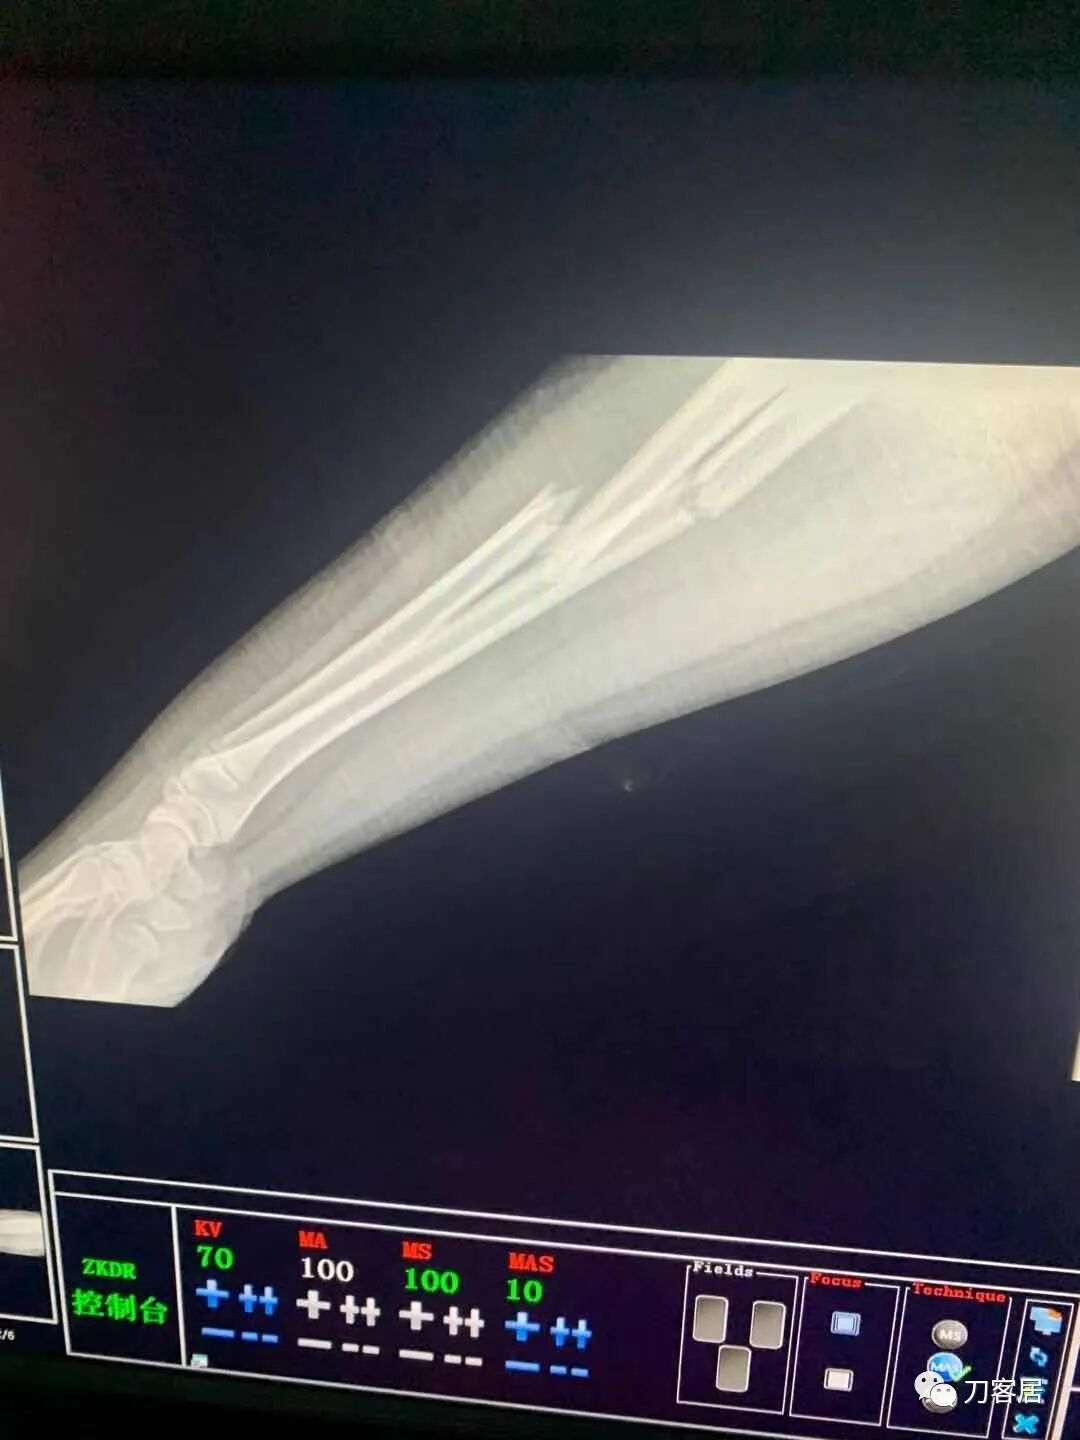

下面是这个6岁孩子,尺桡骨远端双骨折的术前及术后片子和外观照片。

2.  这个骨折处理起来也很简单,单纯的打石膏托或者中医的小夹板,或者正规的包括腕关节和肘关节的管型石膏外固定4周即可治愈该骨折。实在不行,如果这个孩子比较听话,不太调皮的话,用一本书,一个三角巾悬吊固定4周,都可以治愈该骨折。但是给这个患者用外固定架做了手术,而且桡骨远端的几颗克氏针距离骨折线太近,其中一枚克氏针进入到骨折间隙内。从这个术中图片来看,术者的外固定手术技术也有待于进一步的提高。毕竟术者应该还很年轻。从X线片来看,前臂及手的尺侧有不透光影,应该还使用了外固定石膏绷带托,而且我猜测应该是高分子的石膏绷带托,这个是纯属猜测,不一定是对的,不过如何解释前臂尺侧的不透光影呢?如果真是用了石膏绷带外固定的话,那为啥要做手术呢?外固定架术后就不该再用石膏绷带托辅助了。